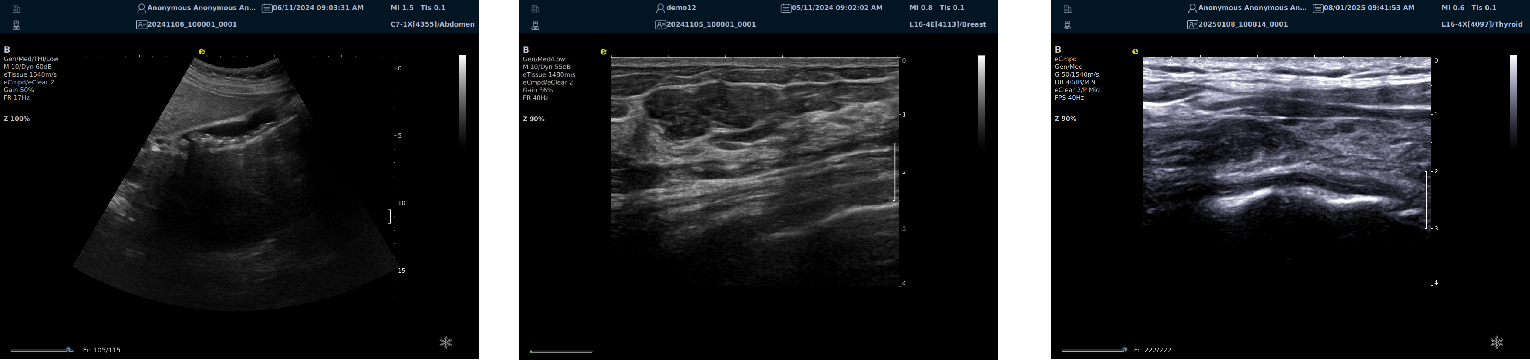

硬件系统架构颠覆、创新软波束形成

image.png

优异的二维图像